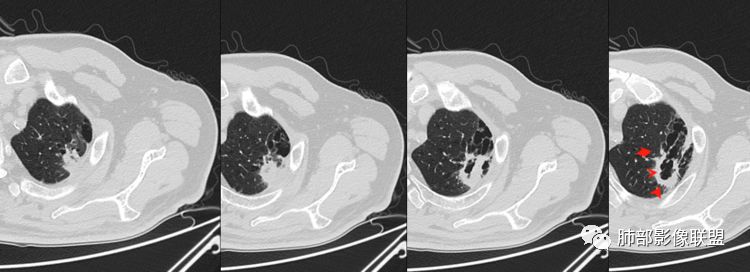

1.左肺上叶应为空腔样病灶。如作为空洞,前下壁并不完整,且与薄壁囊腔壁相延续,整体结合起来看应为厚薄不均匀的较大的空腔样病灶。这样的空腔样病灶应首先怀疑空腔性肺癌。

2.厚壁区可见壁结节及液化坏死。图像未能完整显示小支气管情况,但空腔的存在提示与支气管或多或少还是相通的。

3.病灶轻度环形强化,壁稍显僵硬。灶周显示较清楚,未见磨玻璃晕。

4.可疑胸膜侵犯(栽赃)。